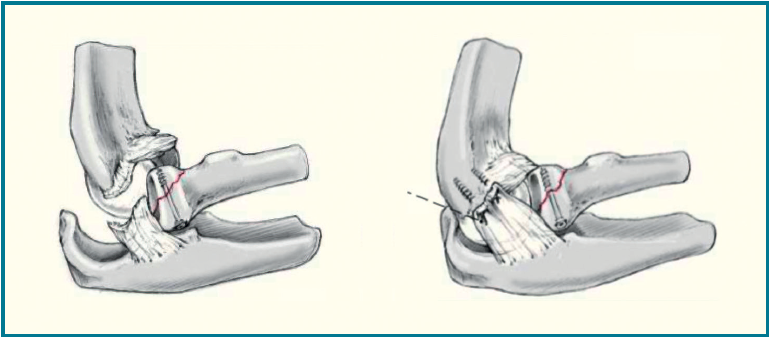

La apófisis coronoides es un factor clave en la estabilidad del codo, ya que contribuye significativamente a la estabilidad anterior y posterolateral. La reparación de la fractura debe ser prioritaria, después de la reducción de la luxación y la evaluación de la cabeza radial. Para guiar la intervención quirúrgica, utilizamos la clasificación de O’Driscoll(17)(Figura 6):

- Tipo I: fractura del vértice de la apófisis coronoides. Dentro de este tipo, se subclasfican en tipo I (< 2 mm) y tipo II (> 2 mm). Como referencia anatómica de importancia, la inserción de la cápsula anterior se sitúa 6,4 mm distal a la punta de la coronoides en promedio(18). Todavía existe controversia sobre la fijación o no de un pequeño fragmento de coronoides (tipo I). Terada N, et al.(19) abogan por una fijación sistemática para conseguir una reducción anatómica y restaurar la estabilidad. En un trabajo previo(20), Regan y Morrey no están a favor de una fijación quirúrgica en este tipo de lesiones. En nuestra experiencia, si es posible, se intenta una reparación para conseguir una reducción anatómica y una restauración de la columna anterior. La reparación se realiza bien con tornillos canulados interfragmentarios o con anclajes transóseos de sutura en aquellos fragmentos de menor tamaño(21,22). La capsulodesis de la cápsula anterior podría ser una alternativa en aquellos casos de inestabilidad posterior persistente o en aquellas fracturas pequeñas de coronoides irreparables que asocian una rotura anterior de la cápsula(23)(Figura 7).